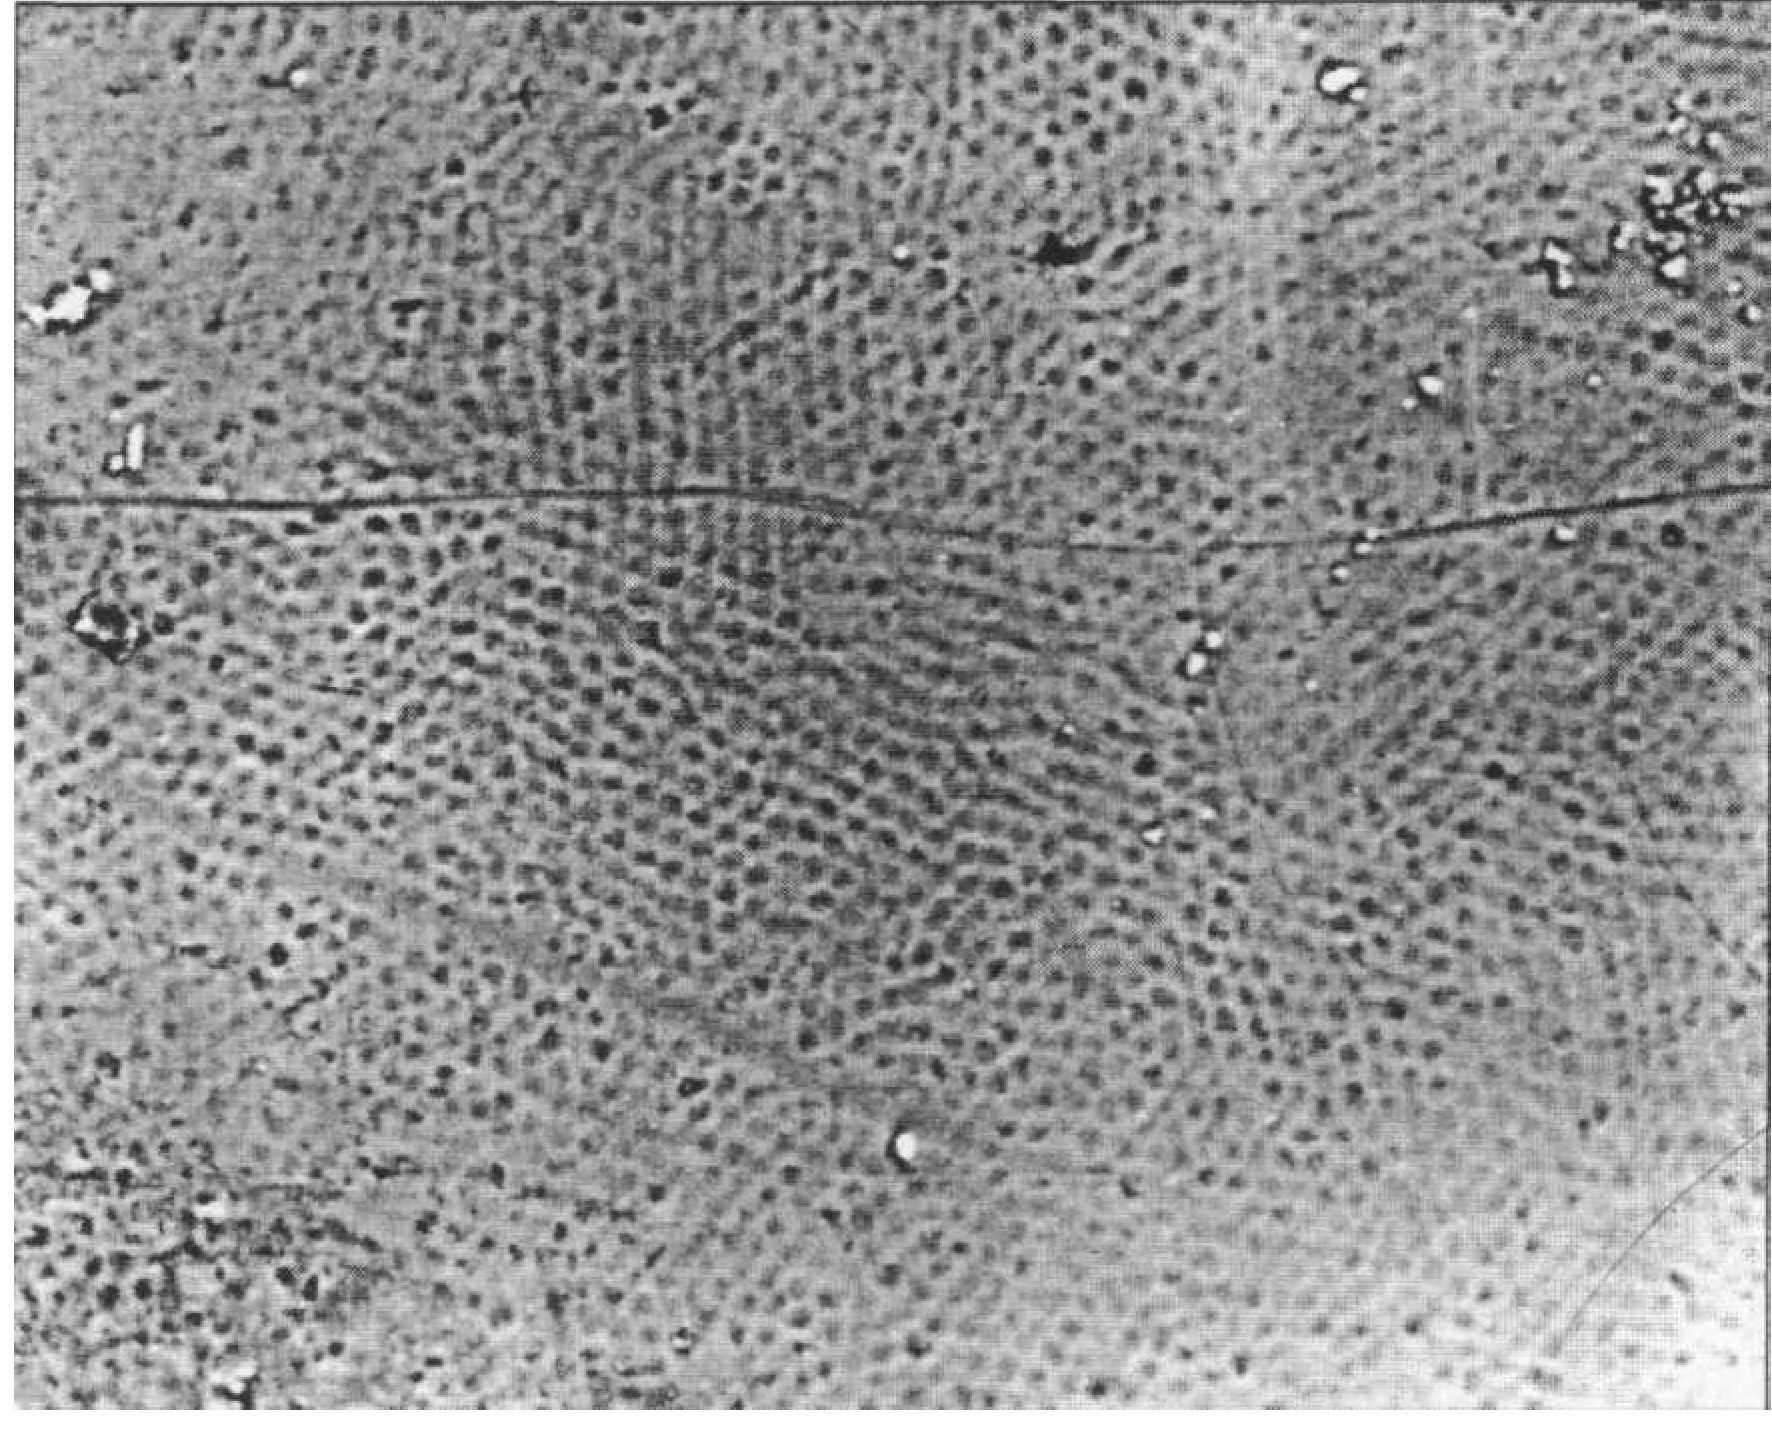

Пелликула устойчива к действию кислот, однако подвержена механическому разрушению. Обычно пелликула тоньше на гребнях перикиматий, а также на контактной и пришеечной поверхностях. Для зубов возрастной группы 7-14 лет характерна регулярная волнистость эмали, образуемая перикиматиями (рис. 81).

СТРУКТУРА ПОВЕРХНОСТИ ЭМАЛИ Поверхность эмали до прорезывания зуба покрыта органической оболочкой, которая носит название кутикула. Ее толщина около 1 мкм. Сразу после прорезывания зуба кутикула стирается, сохраняясь лишь в пришеечной области. Зуб покрывается органической бесклеточной пелликулой (1-10 мкм), которая прочно соединяется с кристаллами поверхностного слоя, проникая в него на глубину 0,1 мкм (рис. 80).